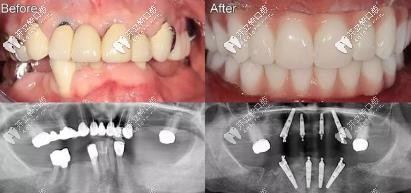

▼案例一:全口all-on-4即刻種植▼

全口all-on-4即刻種植